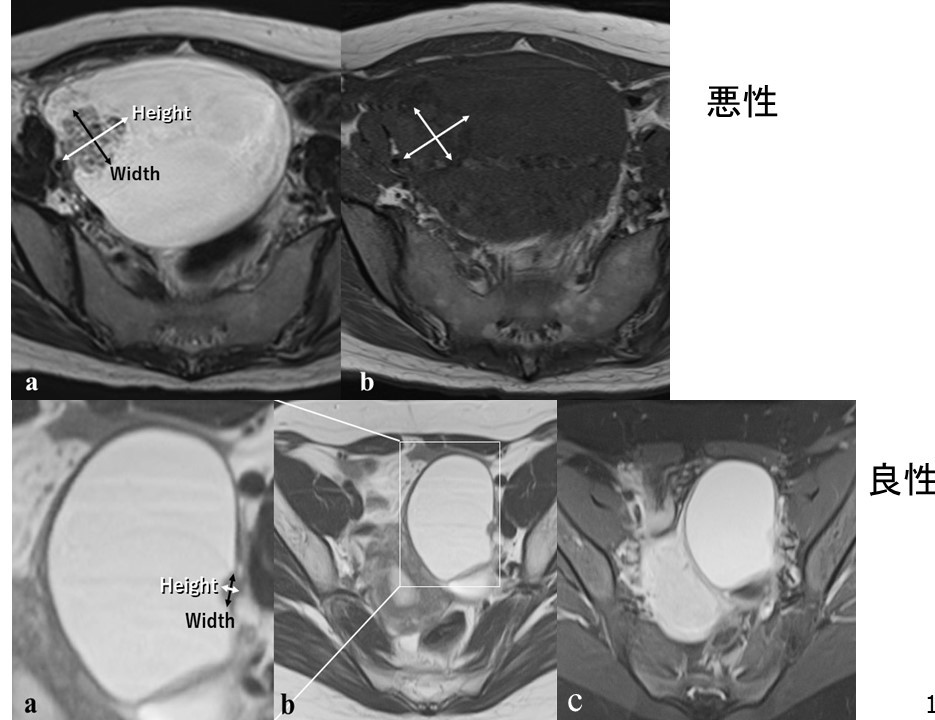

内膜症性嚢胞で壁在結節をみたときの鑑別診断

3. チョコレート嚢胞患者を高次医療機関へ紹介するタイミング:サイズ・エコー輝度・隆起性病変 日本産婦人科医会

6. チョコレート嚢胞に隆起性病変を認めたときに、癌・非癌を区別するにはどうすればいいのか? 日本産婦人科医会

3. チョコレート嚢胞患者を高次医療機関へ紹介するタイミング:サイズ・エコー輝度・隆起性病変 日本産婦人科医会